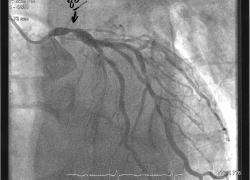

Tests and Limitations for Diving after Heart Surgery | Heart Disease & Diving Chapter 5

Scuba Diving & Heart Disease: Risks of Diving After Cardiac Arrest